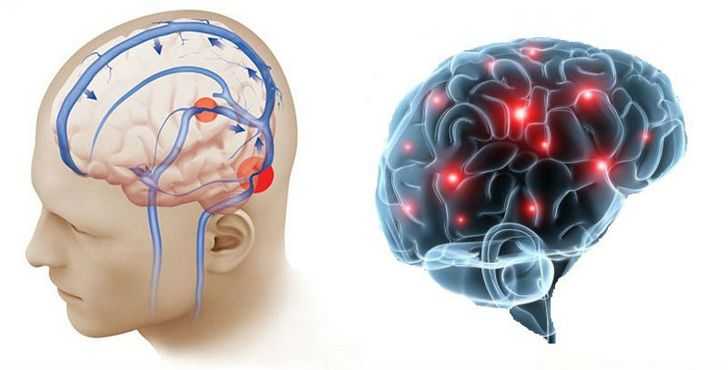

Внутричерепная гипотензия: КТ-исследования и их интерпретация

Раздел: Образы вокруг